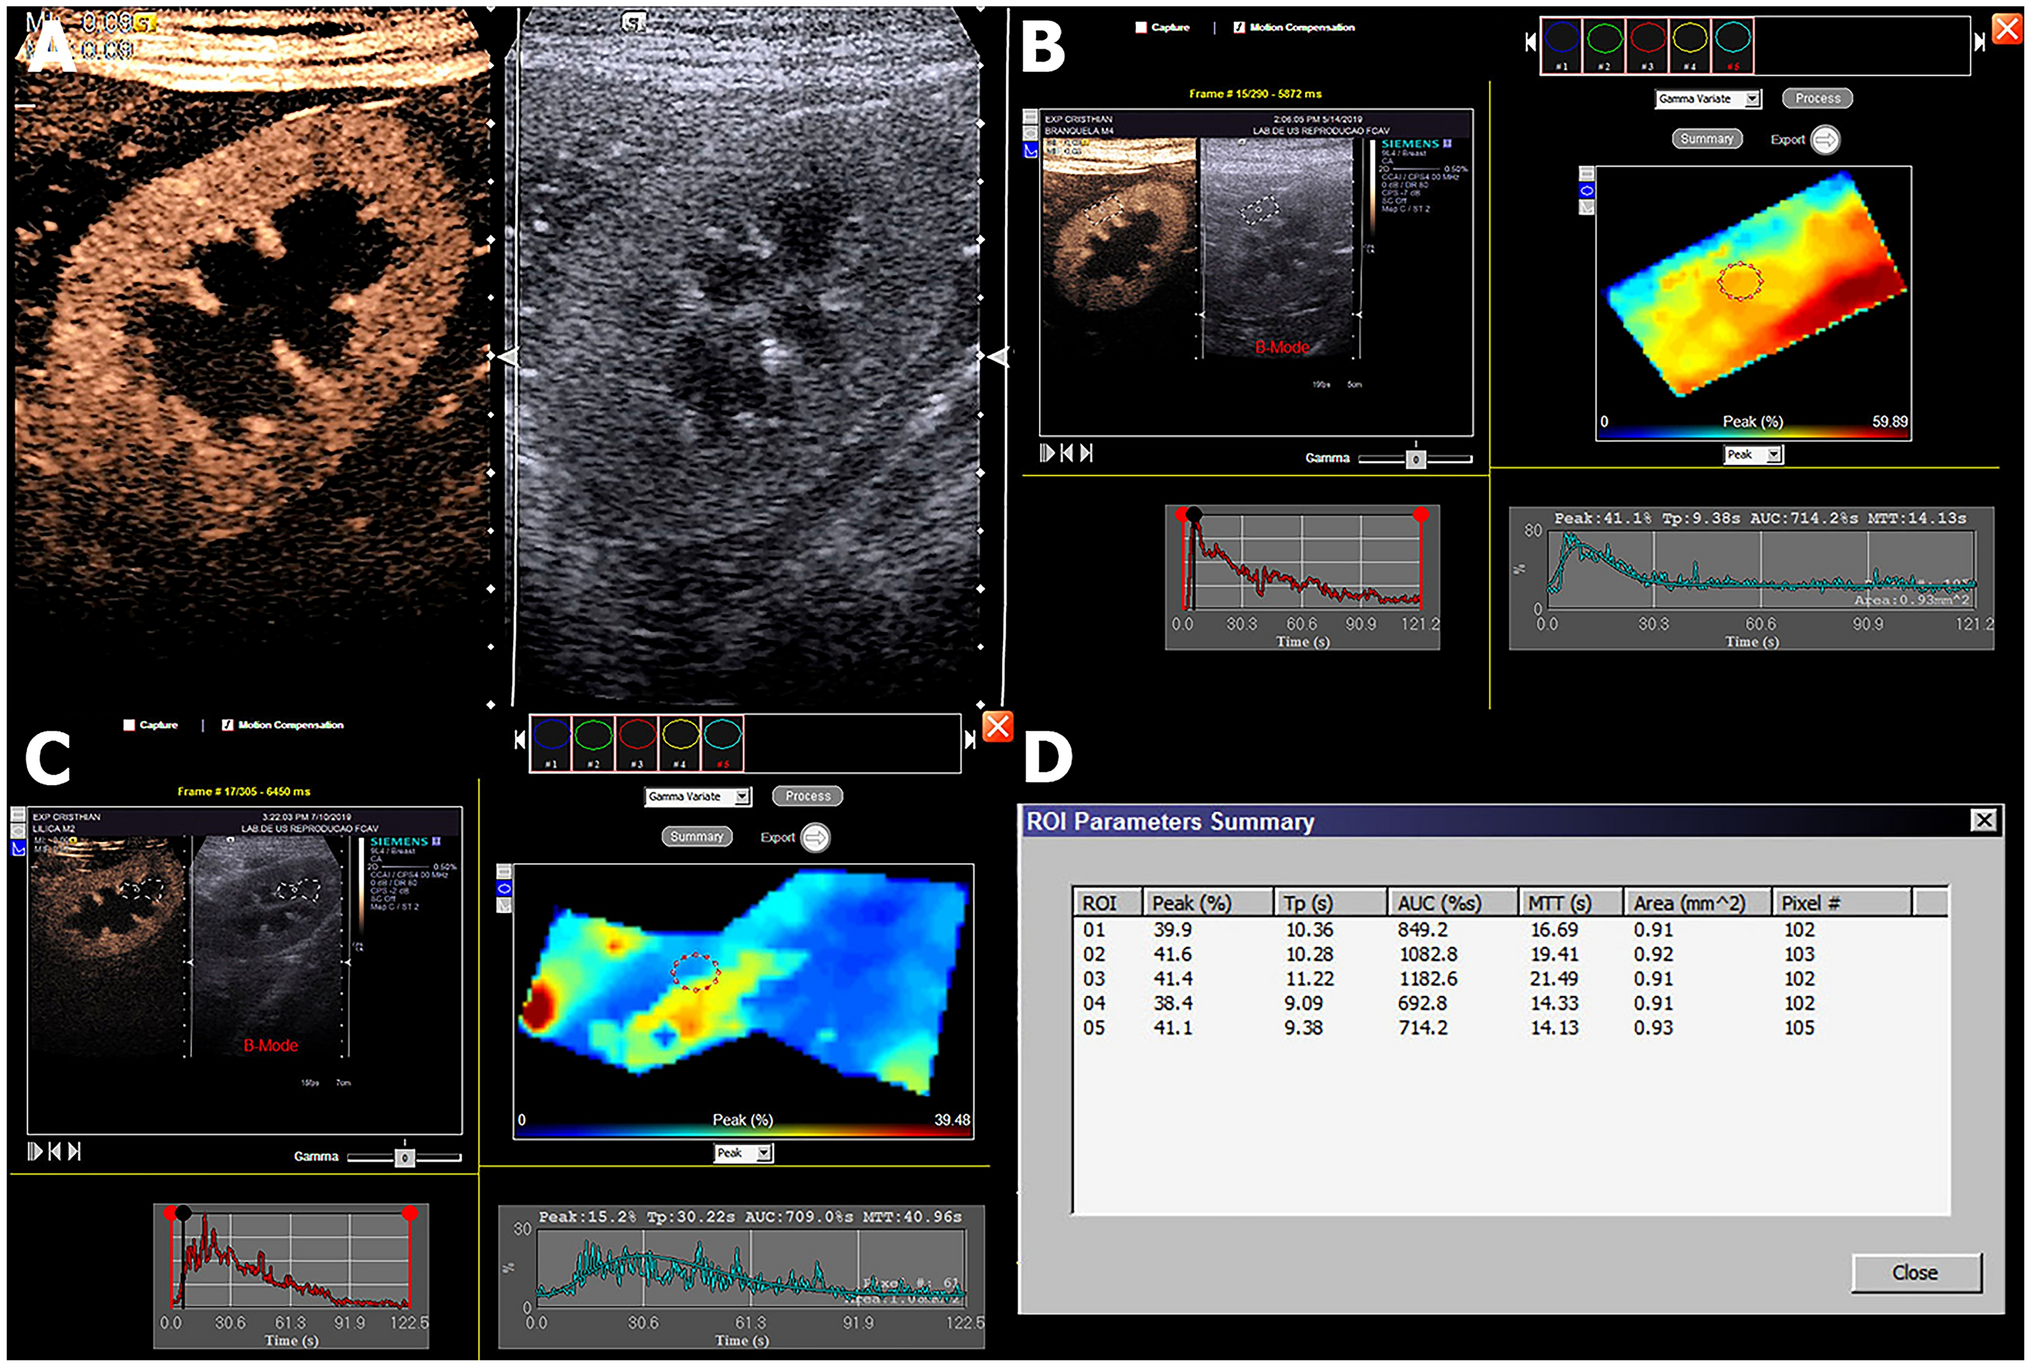

Figure 4

Contrast-enhanced ultrasound (CEUS) evaluations. (A) Qualitative CEUS evaluation of the left kidney, demonstrating the enhanced cortical aspect on the left compared to the B mode on the right on the peak of enhancement. (B) and (C) demonstrate the quantitative analysis of the cortical and medullar portions of the kidney, respectively, obtained by selecting an area of the region of interest (ROI), which is demonstrated in graphics. (D) Quantitative values obtained in the CEUS evaluation.